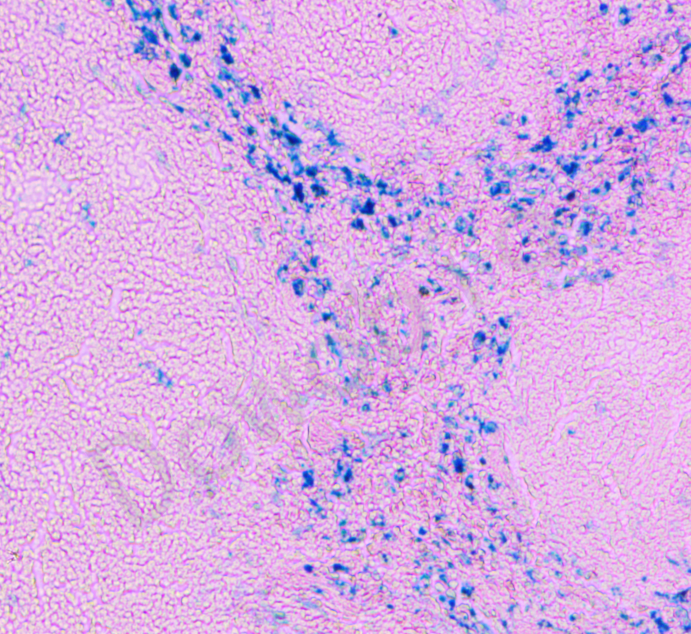

普鲁士蓝铁染色法(Perl's Iron Stain)是检测细胞和组织中非血红素铁的常用组织化学方法之一,通过形成蓝色的普鲁士蓝沉淀检测骨髓及肝、脾、肾等组织细胞中的铁蛋白和含铁血黄素沉积。

亚铁氰化钾溶液使三价铁离子从蛋白质中被稀盐酸分离出来,三价铁与亚铁氰化钾反应,生成一种不溶解的蓝色化合物即三价铁的亚铁氰化物普鲁士蓝。用于显示含铁血黄素。

含铁血黄素呈蓝色,其他组织呈复染颜色。